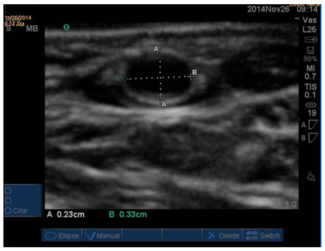

Palpation-guided access of the radial artery (RA) has transradial access (TRA) failure rates averaging 6%-7%.  This study aimed to measure RA and ulnar artery (UA) diameters by ultrasound in a typical American population, in hopes of...